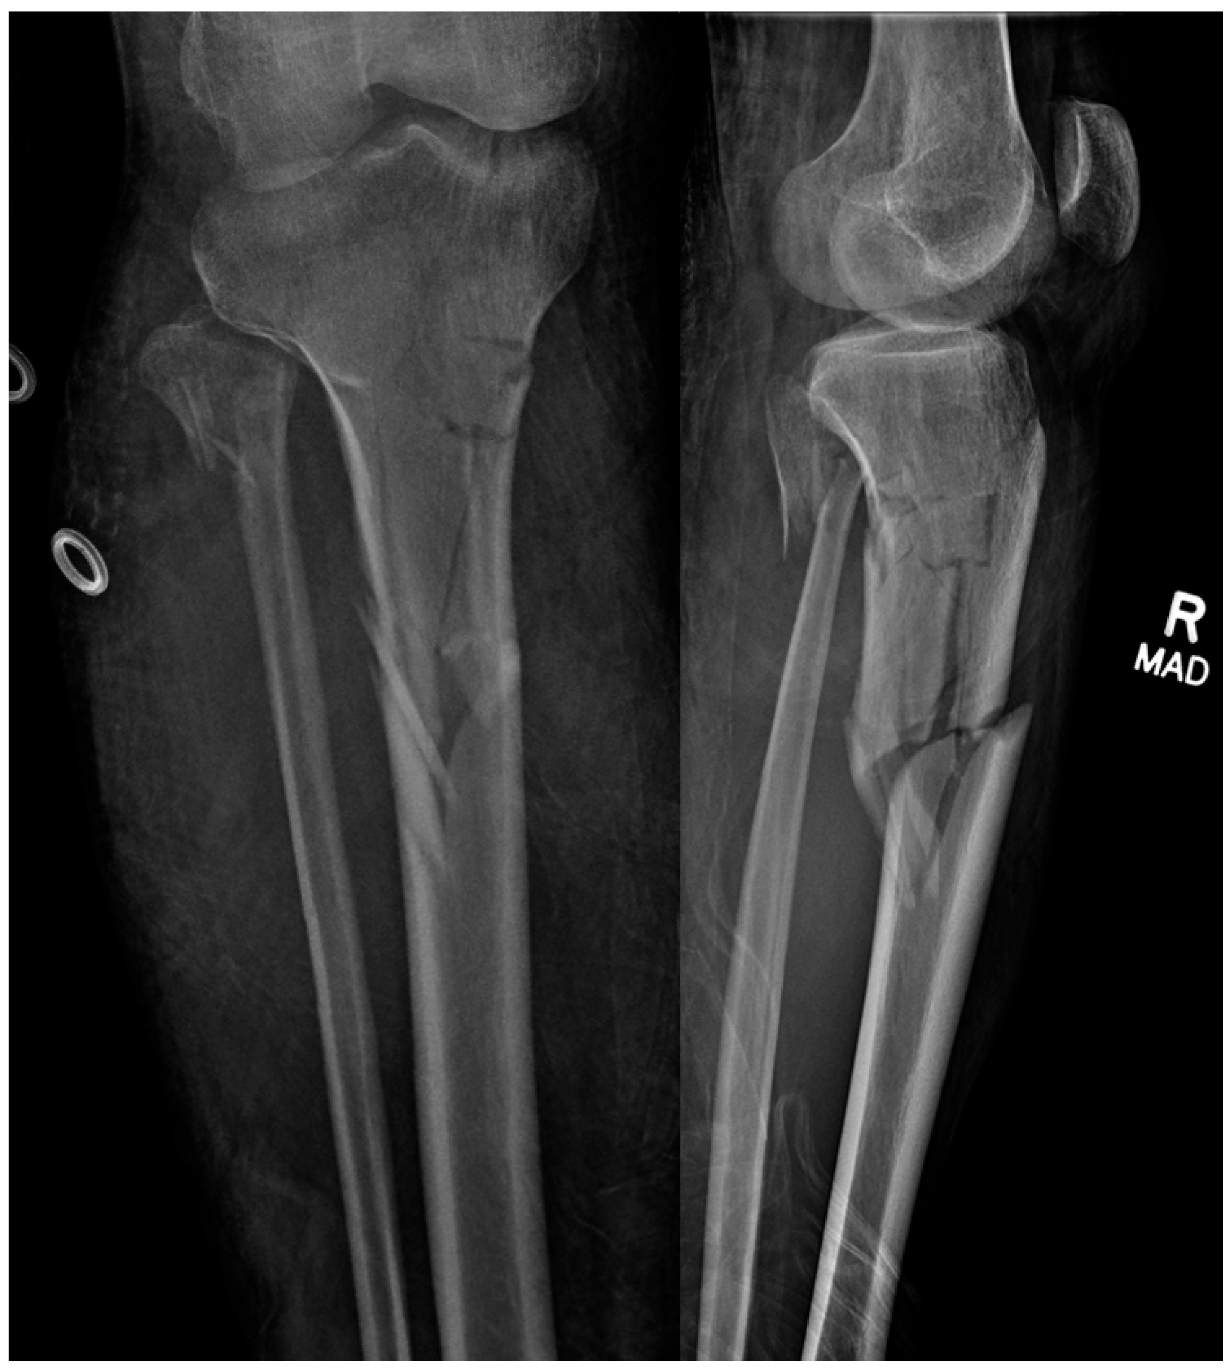

An optimal start site is necessary for a successful surgery, especially when dealing with proximal third metaphyseal fractures (Figure 6). If a start site is close but not perfect, many of the implant systems allow for the insertion of a multi-hole cannula that rotates to make small adjustments in whichever plane necessary, as is being used in Figure 5. It is common knowledge that a medial start site leads to valgus, a lateral start site leads to varus, and a posterior-directed guidewire leads to procurvatum. Although an upward force on the cannula allows for the appropriate start point on the articular margin, the opposite is helpful when using the opening reamer to obtain an entry pathway in line with the sagittal axis of the tibia. If a tight patellofemoral joint is encountered where the cannula is obstructing an accurate start point, the guidewire can be safely inserted without the cannula, and then, the cannula inserted over the top of the wire once positioned. Once the ideal start site is obtained, if the trajectory is not perfect, the wire can first be advanced partially. Next, let the wire be consumed by the opening reamer to allow the reamer to make the adjustments for improved trajectory. The second necessity of treatment of fractures with intramedullary devices is that fracture reduction precedes reaming and nail insertion. Although isthmic fractures reduce well with nail insertion, the authors believe that regardless of fracture location, the fracture should be reduced prior to reaming and nail insertion. This can be achieved with external manipulation, traveling traction, percutaneous clamp application, or formal open reduction with or without plate and screw application. Once the surgery is complete, the authors generously irrigate the joint to remove any reaming debris that may cause post-operative irritation (Figure 7). The quadriceps tendon is closed with a heavy suture, and the skin closed in a standard layered fashion.

Figure 7. Immediate post-operative images.